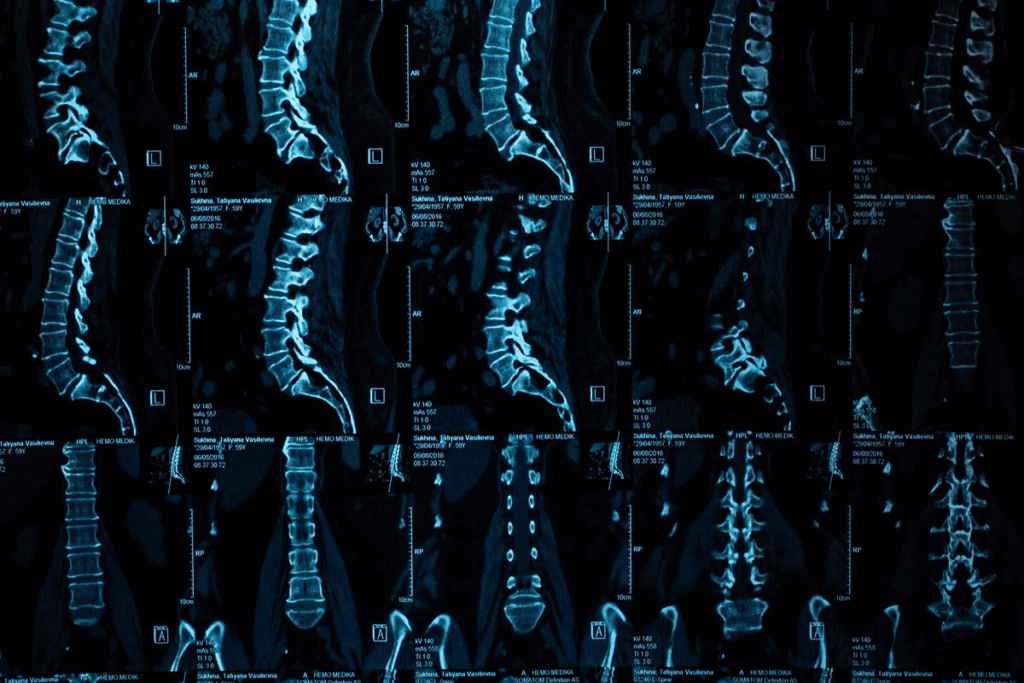

CT scans use X-rays to create detailed images of the body. They are great at finding herniated discs. This makes them a key tool for diagnosing spinal problems.

CT scans combine X-rays from different angles to show cross-sections of the body. This lets us see the spine’s details, like vertebrae and discs. It’s fast and doesn’t hurt, making it a great tool for doctors.

CT scans are good at showing both bones and soft tissues. This helps doctors spot herniated discs. These discs can press on nerves if they bulge out.

CT scans are great at showing the spine’s bones, like vertebrae and joints. They also give info on discs, but might miss soft tissue details. The images can show disc herniations and other problems.

When a CT scan looks for disc herniation, a radiologist checks the images. The detailed images help measure the disc and plan treatment.

When we look at CT scan results, we search for signs of disc herniation. This includes disc bulging or fragments that have moved out. CT scans give us detailed images of the spine. This helps us see how the discs and surrounding areas are doing.

Radiologists check CT scans for herniated discs for specific things. They look at the shape and position of the discs. They check if there’s bulging or herniation that might be pressing on nerves.

They also look at the disc’s density to see if there are any fragments that have come out. We use special software to make these details clearer. This helps us make accurate diagnoses.

They also check for nerve root compression or irritation. This is important because it helps decide the best treatment.

CT scans often show disc bulging, protrusion, and extrusion. Disc bulging means the disc goes beyond its usual size but stays together. Protrusion is when the disc bulges but stays inside its outer layer. Extrusion is worse because the disc material breaks through the outer layer.